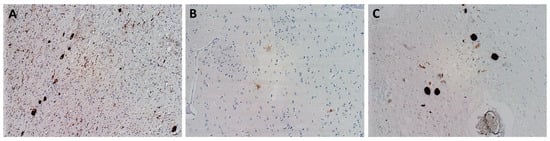

LBD are pathologically characterized by neuronal intracytoplasmic inclusions known as Lewy bodies and Lewy neurites (Figure 2); MSA is primarily associated with oligodendroglial cytoplasmic inclusions (Figure 3).

FTLD-tau are characterized by intraneuronal and/or glial deposits of tau protein. They are generally referred to as “primary tauopathies” (Figure 4). In relation to the predominant isoform of tau protein, which is determined by its posttranslational modifications, they are further subdivided into subtypes 3R and 4R.

Among non-tau FTLD, the most common present deposits are those of TDP-43 protein (Figure 5); deposits of ubiquitin or FUS protein are rarer. Based on this, groups are then further referred to as TDP-43 proteinopathies (FTLD-TDP), ubiquinopathies (FTLD-U), and FUS proteinopathies (FTLD-FUS) [23].

Prion diseases are rapidly progressing diseases characterized by an accumulation of misfolded prion protein PrPSc in brain tissue (Figure 6).